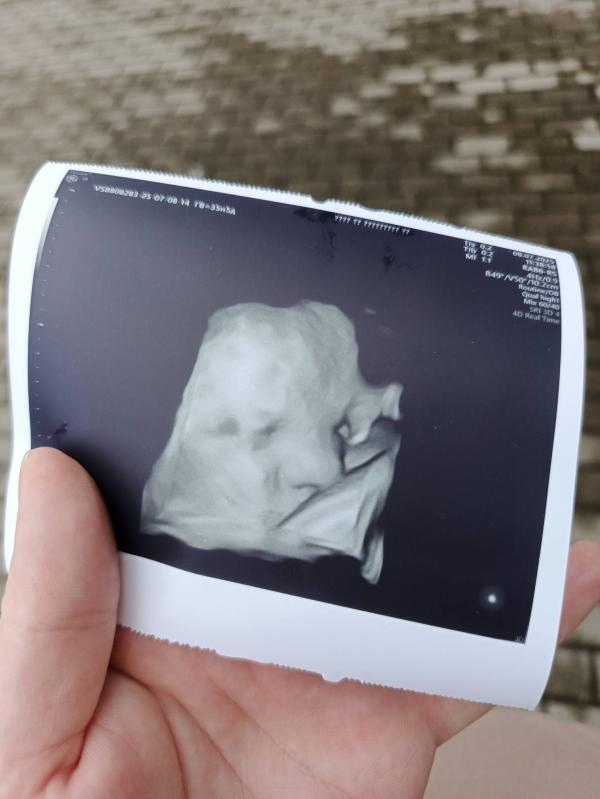

Срок 35,5 н

Вес 3212

Шейка 29

Мы получается очень крупные 🤦

Я верю, конечно имеются погрешности, не спорю.

Но мне всегда хорошо ставили вес.

Перед родами именно этот узист поставила вес и я родила с разницей в 70гр.